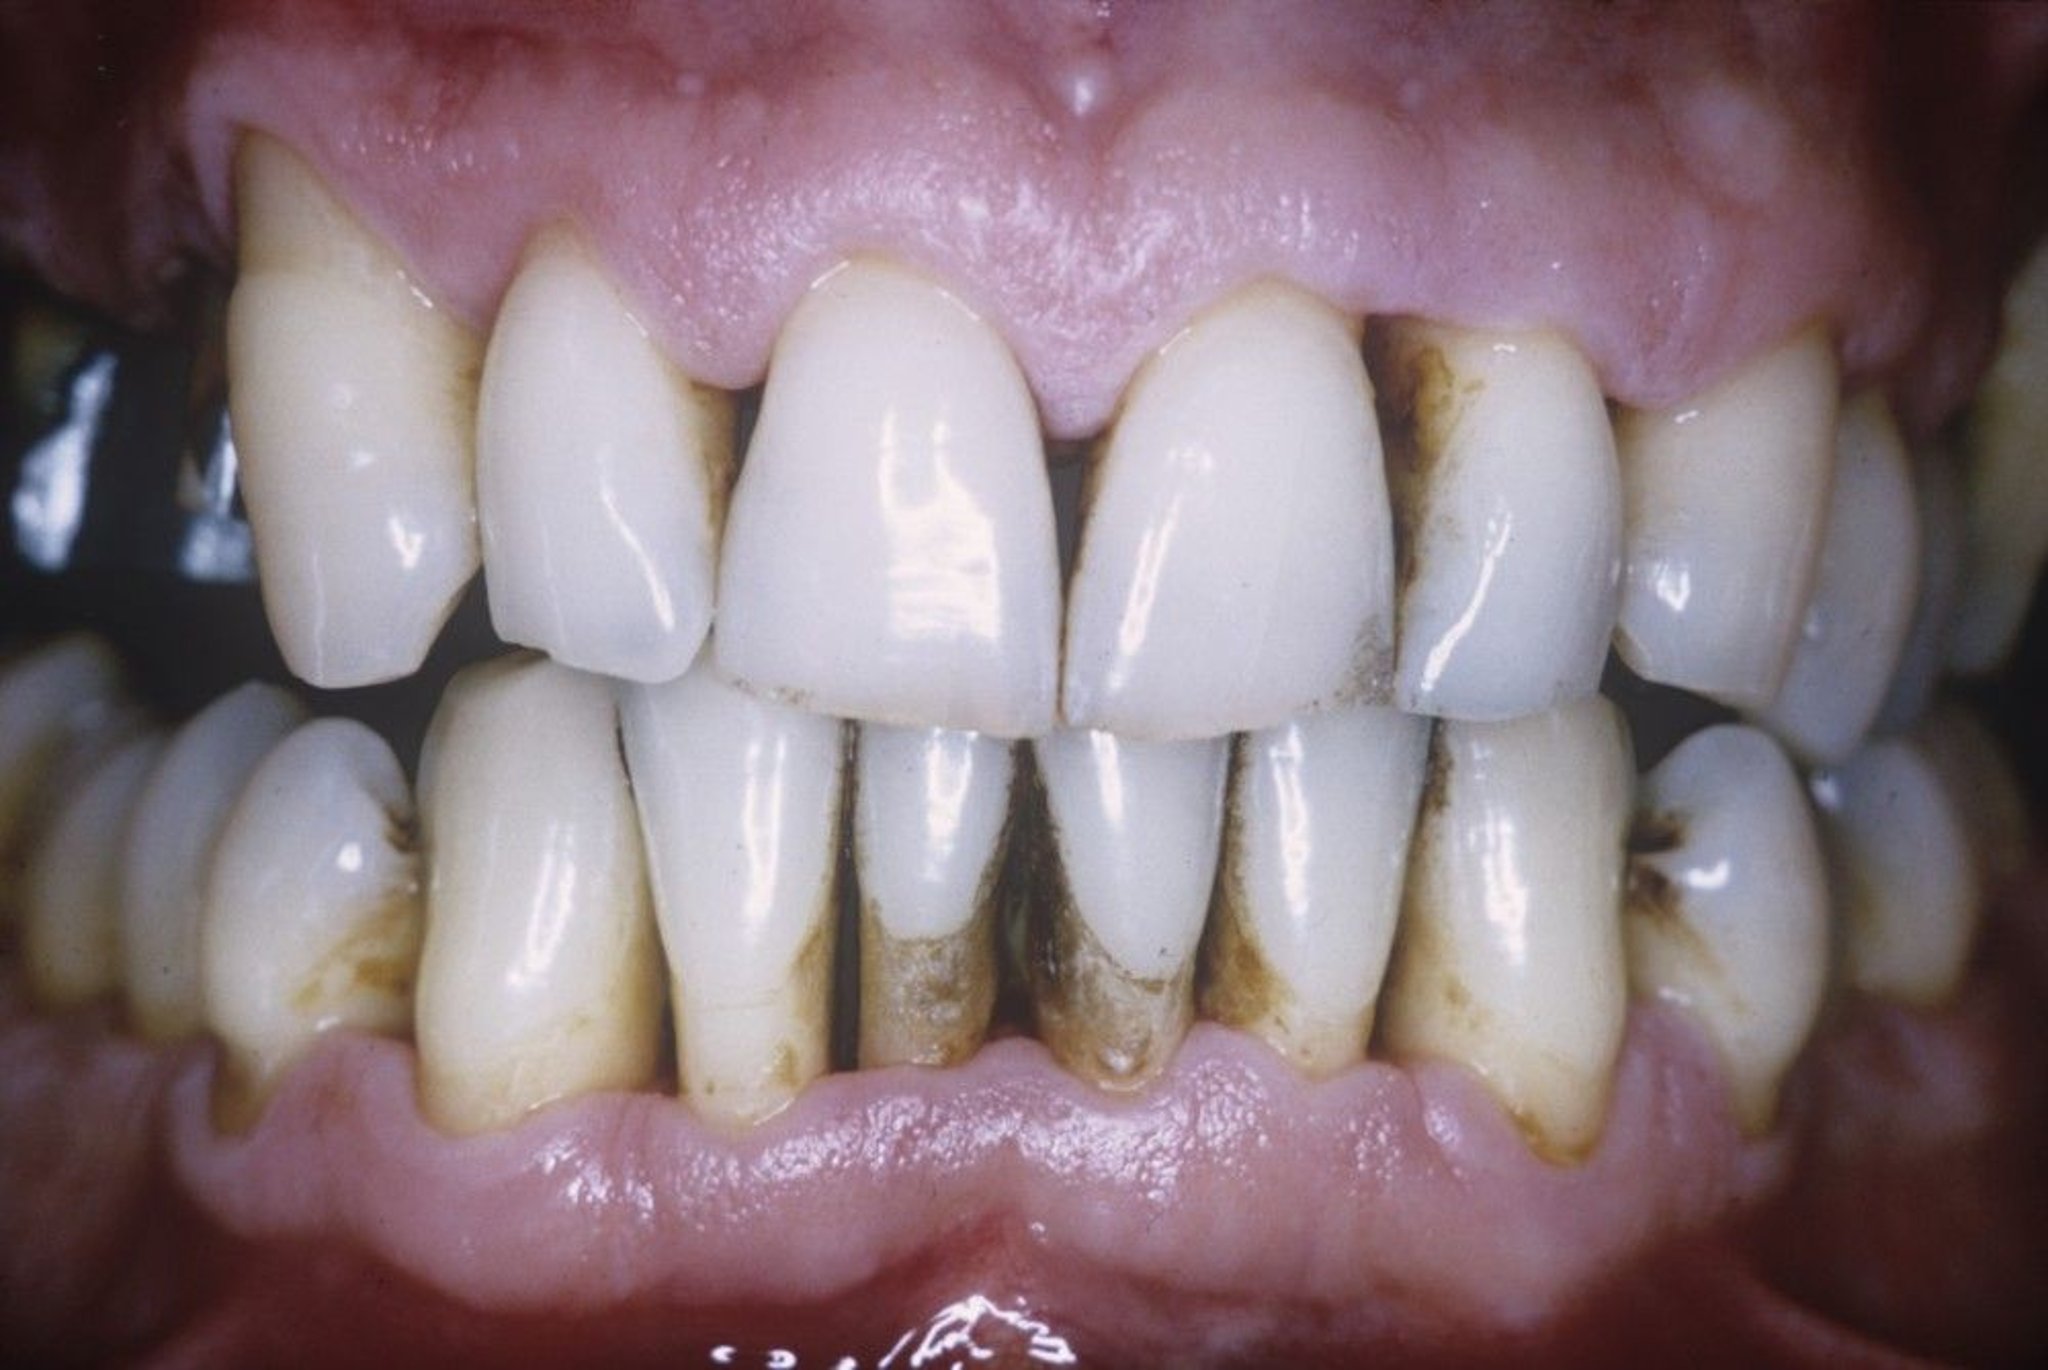

This photo shows a close-up of tissue loss in a person with periodontal disease. Periodontal disease has caused a loss of gum tissue and bone around the teeth.

Dr. W. GREEN/CNRI/SCIENCE PHOTO LIBRARY